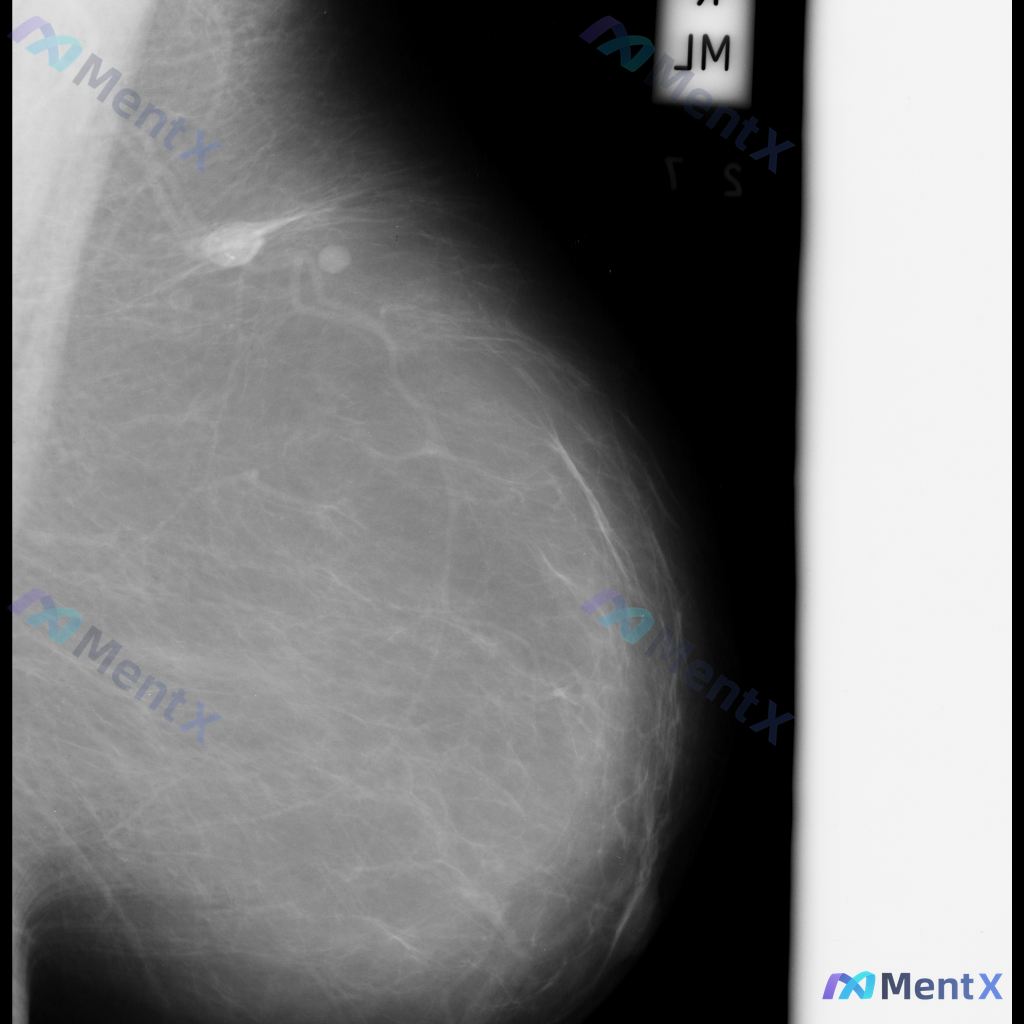

整理了一张乳腺钼靶影像的讨论资料,先和大家分享一下读片描述: 影像可见:不规则、高密度肿块/不对称致密影,伴有毛刺状边缘、结构扭曲和散在钙化。 目前考虑可能存在几种不同的异常方向,想先听听大家的第一反应——单看这组影像特征,你会先往哪种情况考虑? 也可以说说你最关注的是哪一点表现。